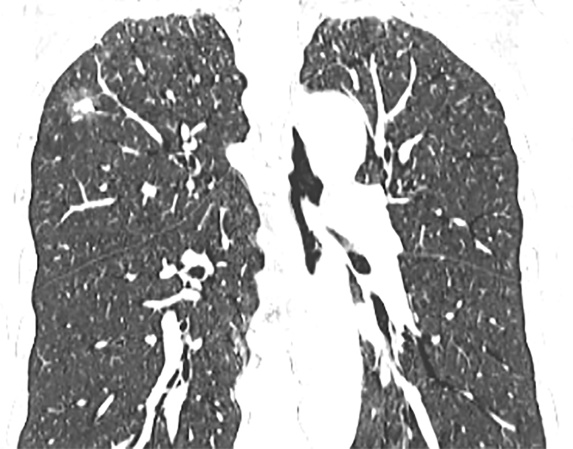

单因素分析显示,CEA、肿瘤最大径、实性成分最大径、CTR、cT分期、边界、分叶征、毛刺征与STAS表达状态显著相关(P均<0.05),将上述特征纳入多因素logistic回归分析,结果表明CEA、肿瘤最大径、cT分期以及毛刺征是STAS阳性的独立预测因素(P均>0.05) (表2)。图1展示了1例STAS阳性患者的CT图像。

(a) (b) (c)

Figure 1. A 57-year-old male patient with STAS-positive lung adenocarcinoma. Axial (a), coronal (b), and sagittal (c) CT images show a part-solid nodule in the right upper lobe, with a well-defined boundary,containing a solid component and peripheral lobulation

1. STAS阳性肺腺癌患者,男,57岁。横轴位(a)、冠状位(b)、及矢状位(c) CT图像示右肺上叶部分实性结节,边界清晰,内可见实性成分,周边可见分叶征